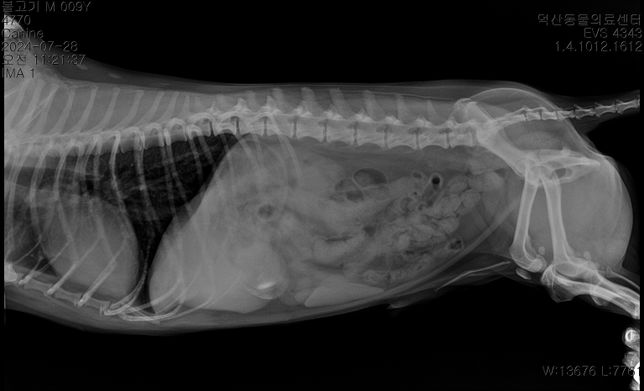

- 반려동물 건강반려동물Q. 강아지 담낭 찌꺼기가 차있다고 하는데 수술해야 하는 정도일까요? 초음파로도 보인다고 합니다안녕하세요 강아지 담낭 찌꺼기가 차있다고 하는데 수술해야 하는 정도일까요? 초음파로도 보인다고 합니다엑스레이 사진에서 저정도 보이면 바로 수술해야한다고 하는데 걱정입니다보통 몇일 입원하나요?